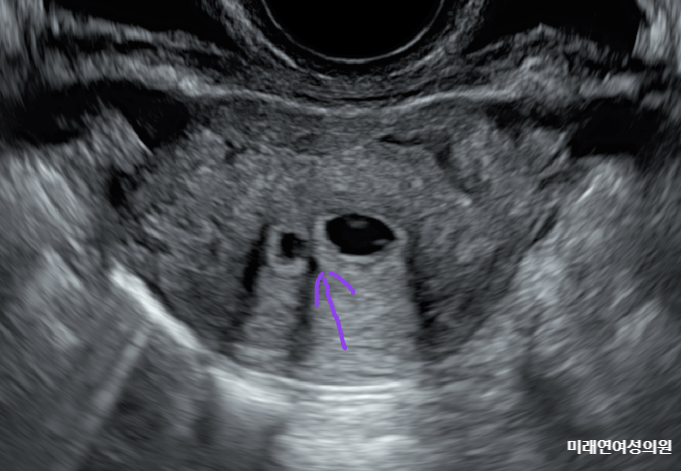

자궁내 유착 - 진단 (생리식염수 주입 초음파 검사)

안녕하세요 미래연 닥터맘 석원장입니다.^^ 글을 자주 쓰다 보니... 이런 스티커가 궁금해져서... ^^::::: ...